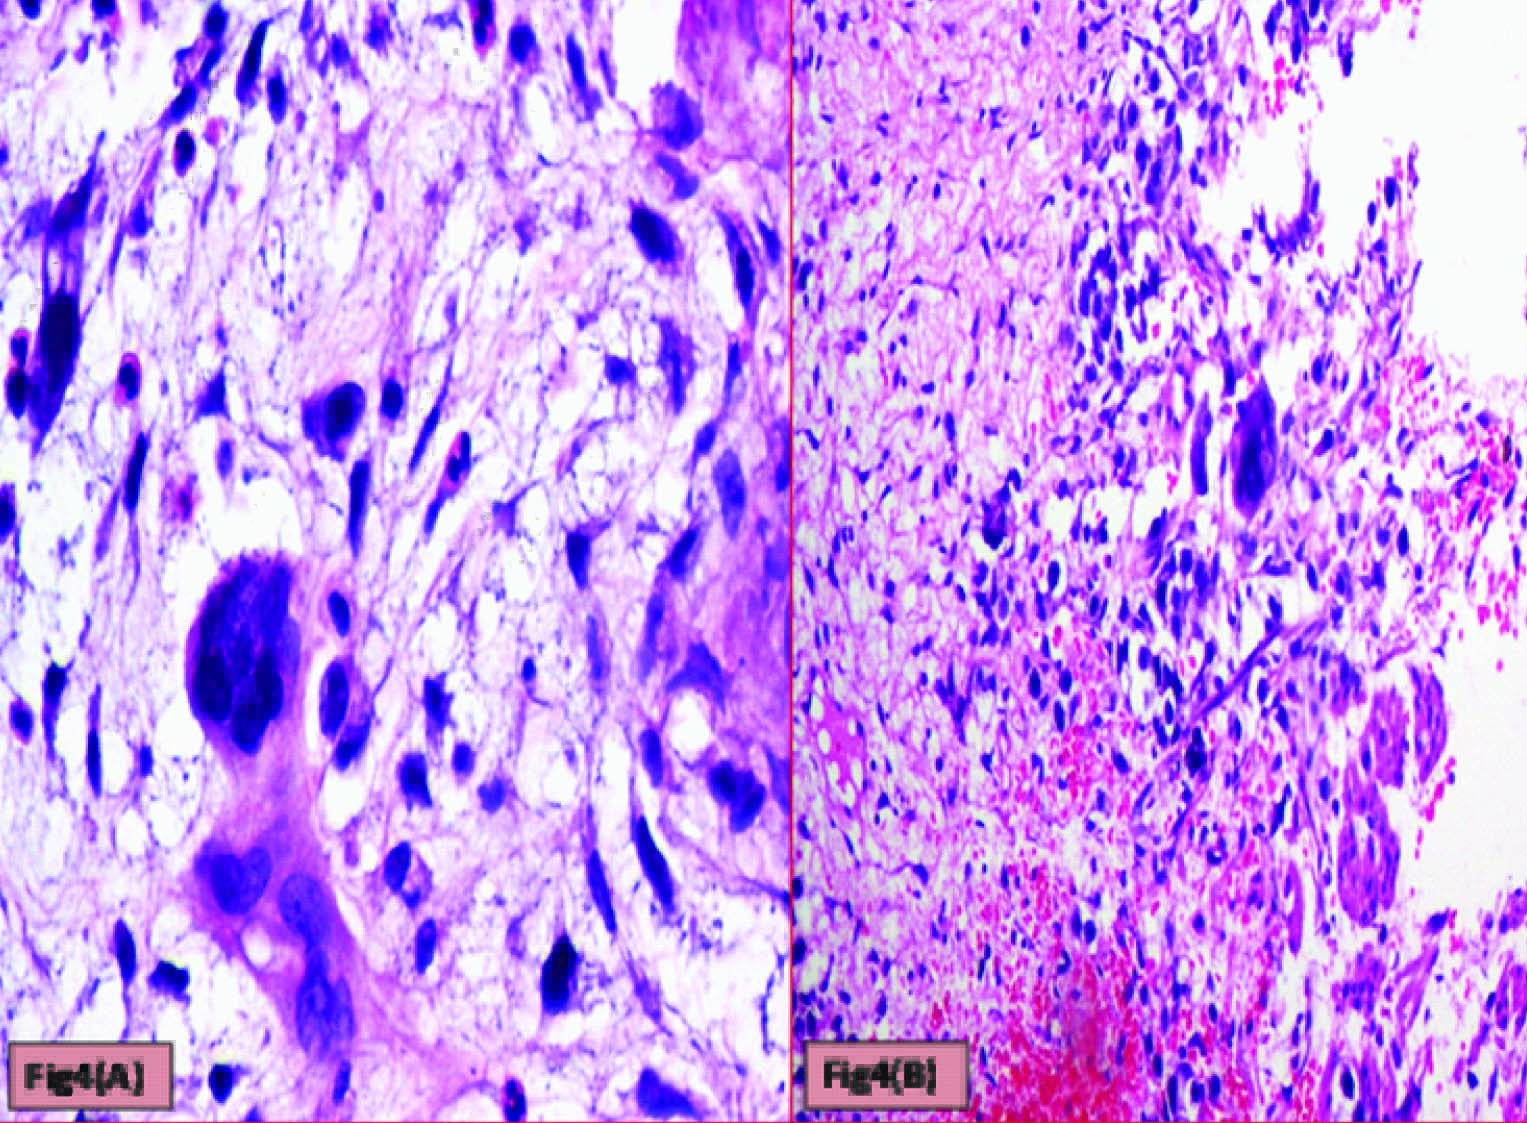

Histopathological evaluation showed a tumour with monomorphic large germ cells with enlarged centrally located vesicular nucleus, prominent nucleolus and moderate clear cytoplasm arranged in sheets, divided into lobules by fibrous septa with lymphocytic infiltrates and stromal hemorrhage; foam cells were also noted [Table/Fig-2a,b]. Also seen were immature glands lined by columnar cells with hyperchromatic nuclei and subnuclear- vacuolation surrounded by atypical spindle shaped stromal cells and foci of immature cartilage [Table/Fig-3]. Large areas of sinusoidal vascular channels surrounded by cytotrophoblasts and syncytiotrophoblasts were seen suggestive of choriocarcinoma [Table/Fig-4a,b].

Cytotrophoblasts & Syncytiotrophoblasts with (a) Myxoid areas (H&E: 400X) (b) Hemorrhagic areas (H&E: 200X)